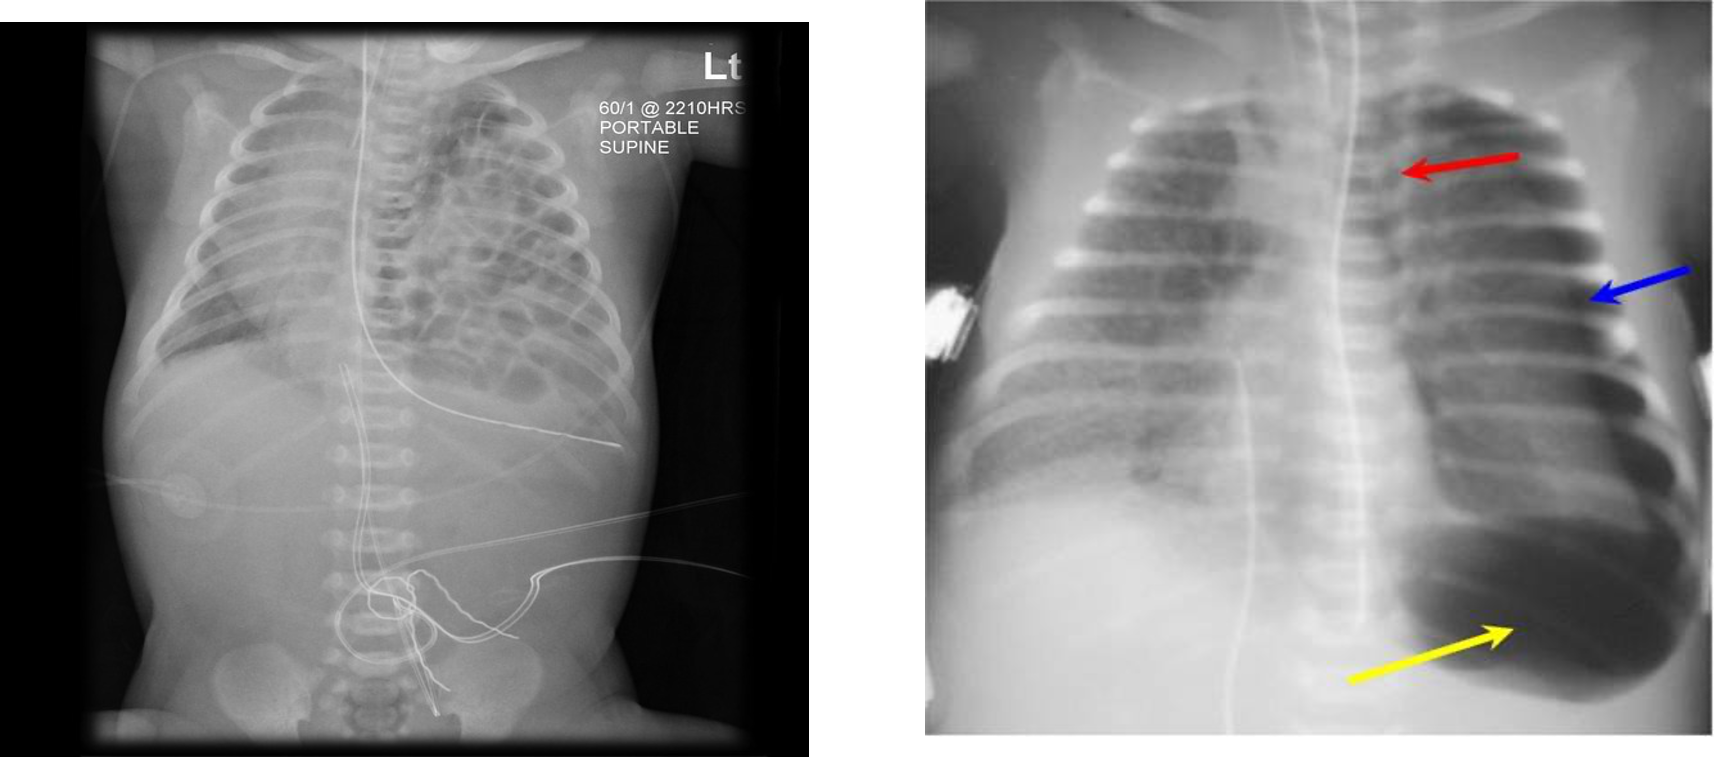

- A chest radiograph: cardiomegaly, narrow mediastinum, and increased pulmonary vasculature. ECG: RAD and RVH